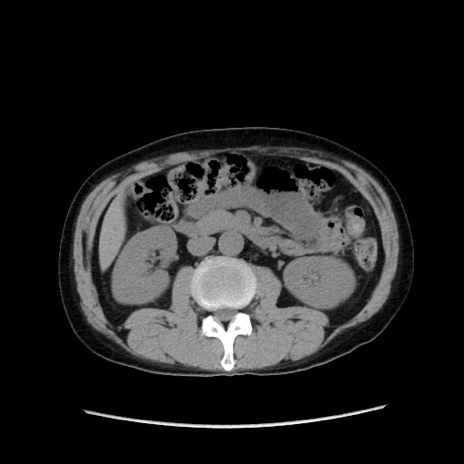

症例37(横断像)

【症例】40歳代 男性

【主訴】腹痛

【現病歴】4時間ほど前に電車に乗車中に臍部上より腹痛出現。徐々に増悪し起立困難となり、救急外来受診。生ものは数日食べていない。今朝お雑煮を食べた。

【身体所見】BT 36.8℃、BP 117/84mmHg、HR 91/min、SpO2 97%、苦悶様、腹部:臍上部広範囲圧痛あり、反跳痛±

【データ】WBC 8100、CRP 0.03